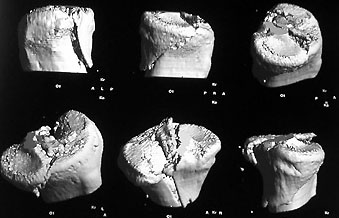

Im 3D-Modell des Schienbeinkopfes vom 24.1.2002 sieht man ebenfalls gut die Eminenz, im unteren Bild mit den oberen Pfeilen markiert (für grössere Fassungen auf die Bilder klicken). Im unteren Bild ist links aussen ein altes Schraubenloch erkennbar (Pfeil links unten), im mittleren Modell zudem die verheilte Bruchstelle (drei Pfeile).

Grössere Fassung Bild 1 / Grössere Fassung Bild 2